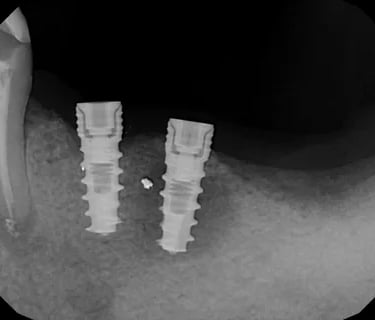

Pérdida de múltiples dientes

La pérdida de múltiples dientes es la ausencia de varios dientes que puede ser resultado de caries, enfermedades periodontales o traumatismos.

Los pacientes notan varios espacios vacíos en su boca, lo que afecta su capacidad para masticar y hablar adecuadamente.

El tratamiento incluye la colocación de varios implantes dentales para restaurar la función y la estética.